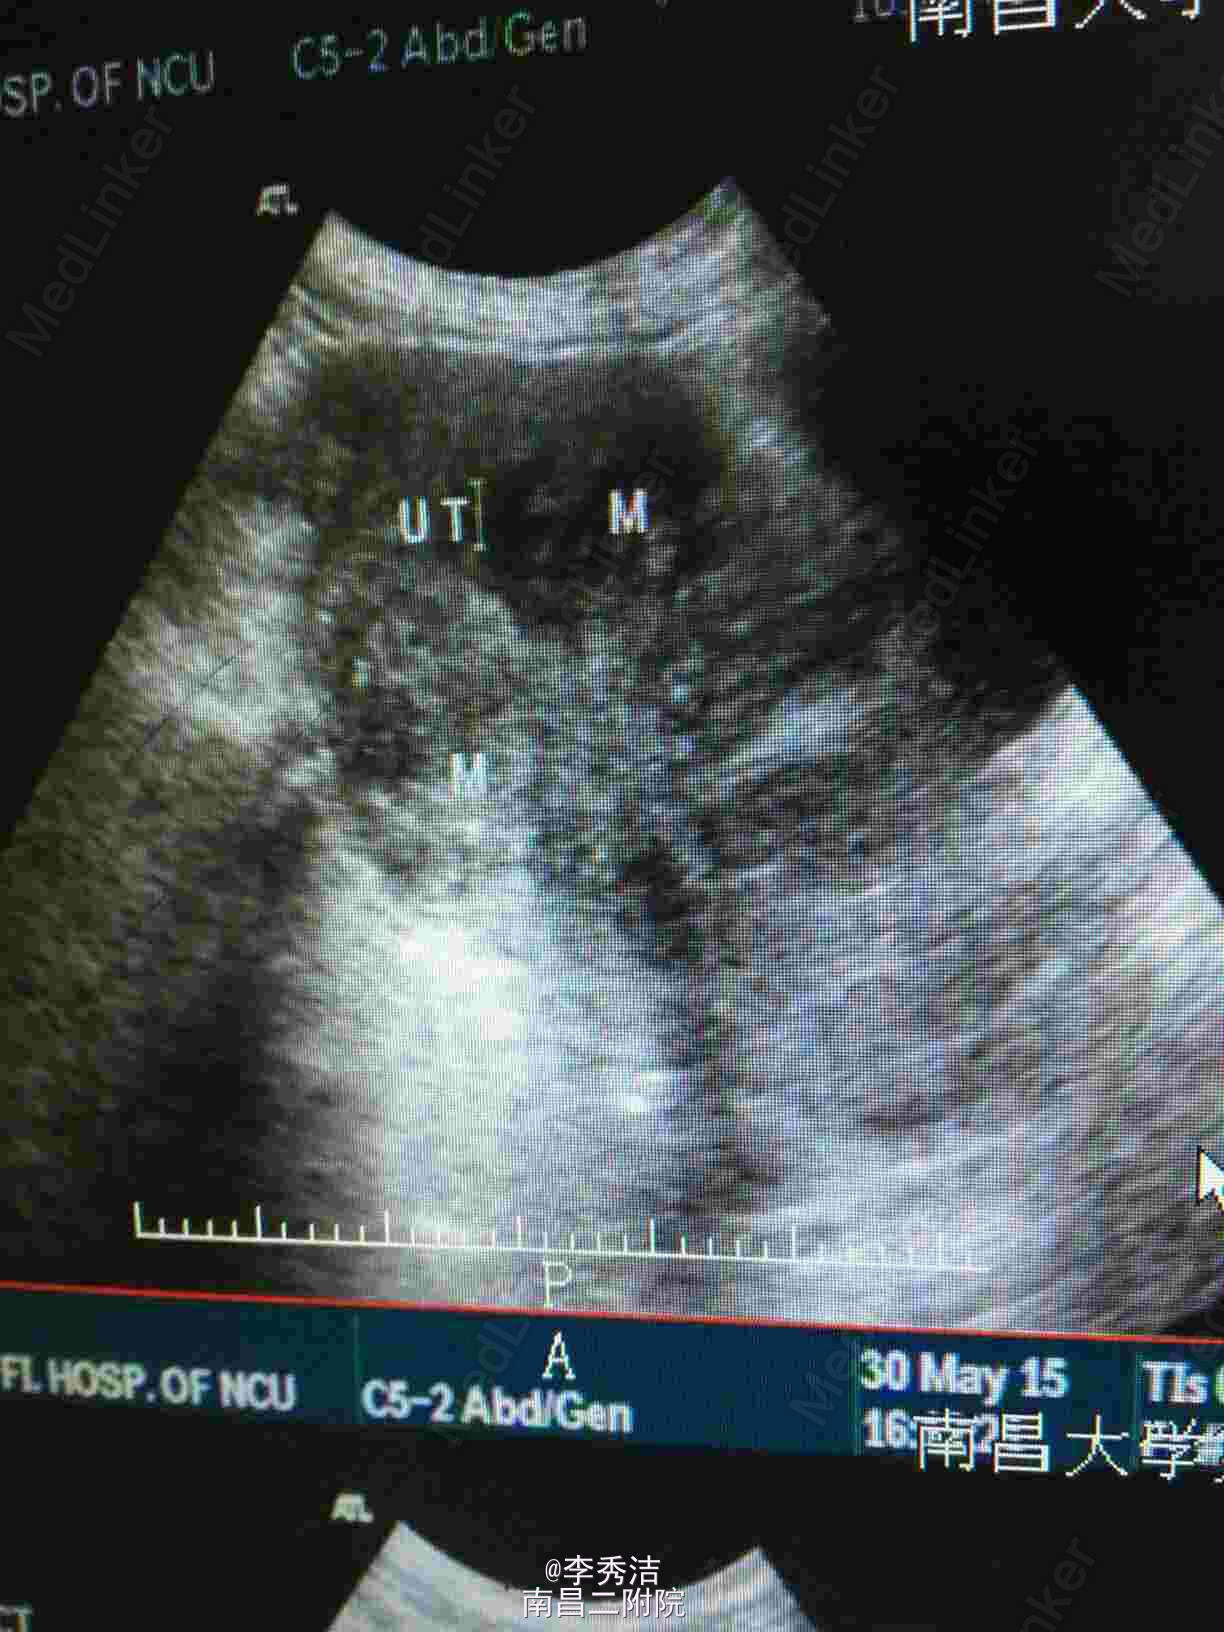

妇科检查:外阴:已婚已产史,阴道:畅软,少量白色分泌物,宫颈:少糜,6点钟方向见纳氏囊肿,宫体:前位,孕4月大小,无压痛,活动,双附件未及异常。彩超示:子宫多发肌瘤。

诊断:多发性子宫肌瘤。